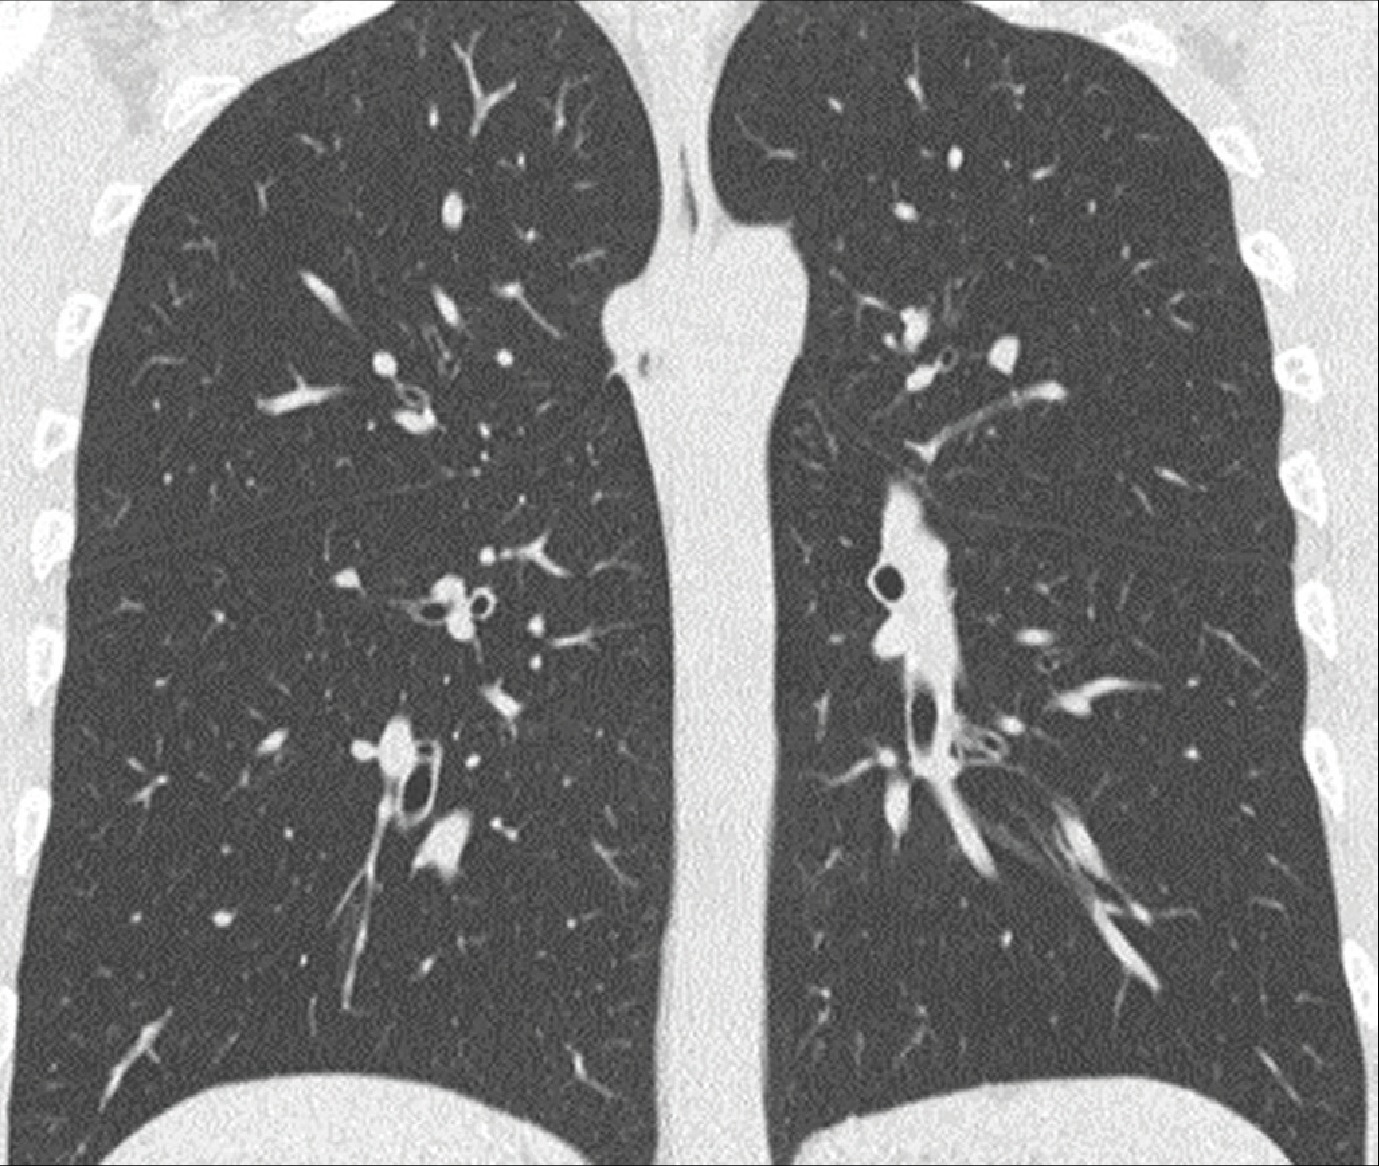

Een HRCT-scan maakt gebruik van röntgenstraling en een computer om zeer scherpe beelden van extra dunne doorsneden van de longen te kunnen maken. In tegenstelling tot de traditionele röntgenfoto van de borstkas, kunnen met behulp van een HRCT-scan vele kleine details in de longen zichtbaar worden gemaakt die behulpzaam kunnen zijn bij het stellen van de diagnose.

HRCT-scan van de borstkas